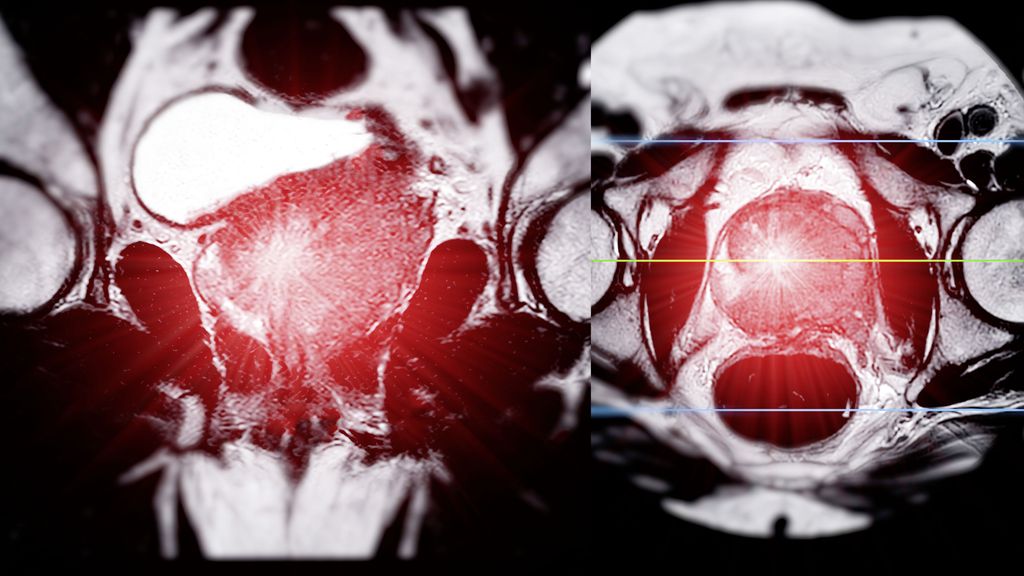

Focus: cardiomyopathie hypertrophique

Dans notre focus sur la cardiomyopathie hypertrophique (CMH), nous avons réuni pour vous des articles pertinents sur cette maladie. À l’occasion de nouvelles possibilités thérapeutiques, de nombreux aspects...